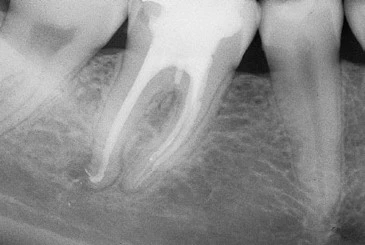

Đọc tiếpRăng cối lớn một hàm dưới Mở xoang tủy nhìn chung răng cối lớn một hàm dưới có 2 chân…